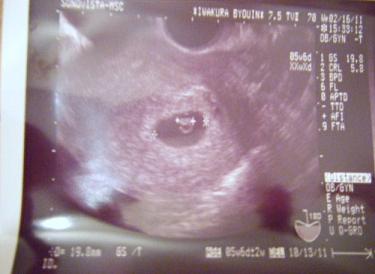

まだ6週目ですがつわりも眠気も頻尿も、足の付け根の痛みも腰の痛みもありません。

妊娠2か月